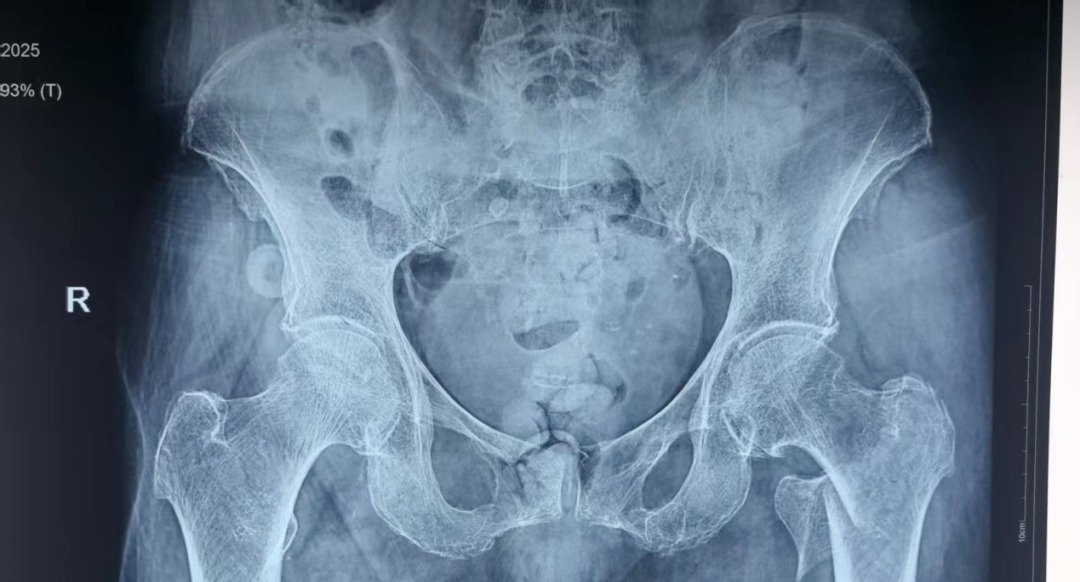

近日,患者李某某在即将迎来自己103岁生日时,不慎在家摔倒导致左髋关节疼痛伴活动受限,就诊于当地医院诊断为左侧股骨转子间骨折,因患者为超高龄老人,当地医院考虑手术风险大,建议转诊上级医院进行治疗。患者家属遂联系120转诊至成人探花

为防止坠积性肺炎、褥疮、深静脉血栓等并发症发生,杨自权主任团队在患者入院后,积极完善术前准备,经过医务处的组织和血管外科、麻醉科、康复科等多学科的MDT合作,手术时间定于患者入院第三天。2022年,美国AAOS(美国骨科医师协会)指南强烈推荐老年股骨转子间骨折(稳定或不稳定)采用髓内钉内固定。因此,杨自权主任团队拟行股骨转子间骨折闭合复位髓内钉内固定微创手术。

手术当日,杨自权主任团队借助丰富的手术经验,术前在牵引床、G臂辅助下迅速给予患者闭合复位骨折断端,结合经典的“2-1-1”微创手术切口实施手术,手术过程顺利,G臂透视可见骨折复位满意,髓内钉位置满意。术后患者顺利出院,安返家中。